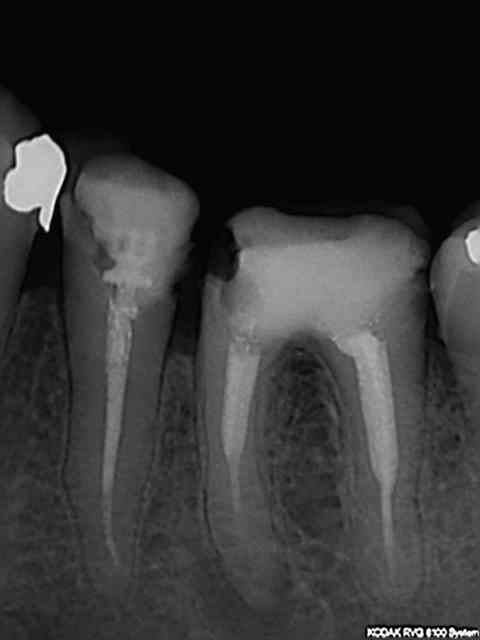

Soigné mon beauf pulpec 17 (pète c... mais ca s'est bien passé........)

La 27 pas du tout dans la meme config, 4 racines 2 vestibulaires et 2 palatines.

Bilan sx pété dans la mésio - palatine (ca faisit une éternité que ca ne m'était pas arrivé) et racine disto-vestibulaire résorbée par la 8 (j'ai cru qu'en plus j'avais fait un faux canal).

26 extraite dans la foulée (j'ai viré la merde de screw-post amalgame qui tenait à un fil pour m’apercevoir qu'elle était fracturée dans le sens mésio-distal) pour le reste , stand- by et un ou deux clous à prévoir.)

Mmmmm, la suite RTE 36 avec pèche sur le mésial (quoique j'hésite à perturber le fragile équilibre d'un 4eme, avec ce qui s'est passé en face.....)l'avantage c'est que la 26 n'est plus là car la bouse d'amalgame avait gagné son duel d'usure sur la bouse de composite.)